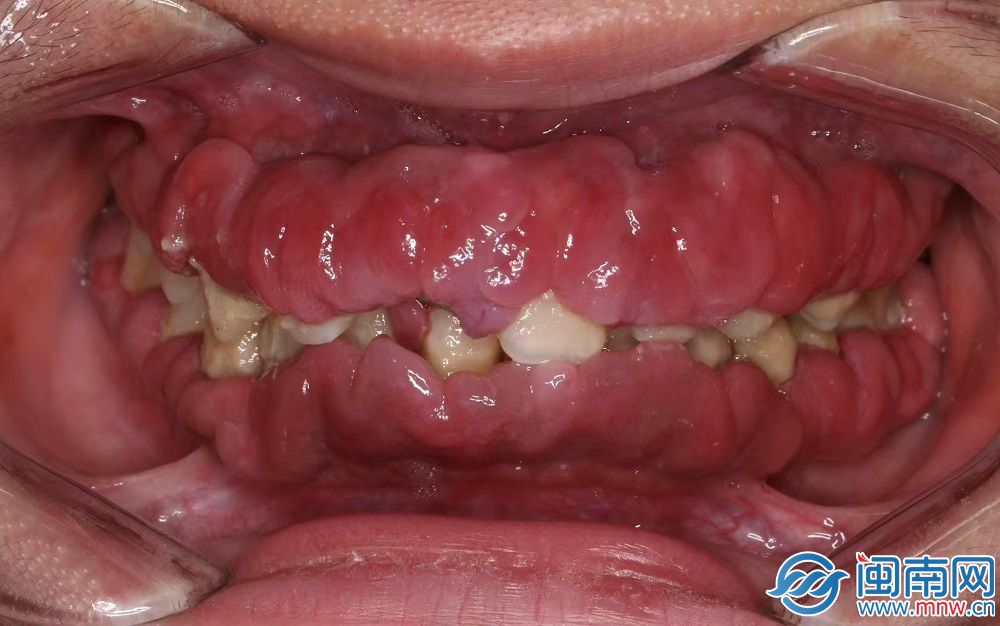

“胖嘟嘟”的牙龈包裹住牙齿(医生供图)

陈医生介绍,小强的牙龈红肿、圆钝,不是紧贴着牙齿,而是松松垮垮,看起来“胖嘟嘟”的,暗红色的牙龈包裹着牙齿,几乎看不到牙齿。仔细看,牙齿被一层厚厚的软垢包绕着,有些牙已经开始松动。